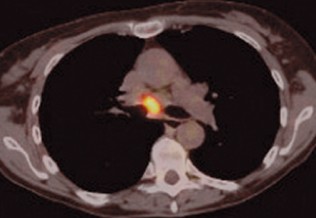

L’objectif principal du dépistage du cancer du sein est la diminution de la mortalité spécifique en détectant le cancer à un stade très précoce dans une population supposée en bonne santé. Le diagnostic de cancer dès le début de son développement permet d’éviter les traitements lourds et augmente les chances de guérison. Plusieurs études scientifiques bien conduites ont démontré l’efficacité d’un tel dépistage sur la réduction de la mortalité féminine par cancer du sein.